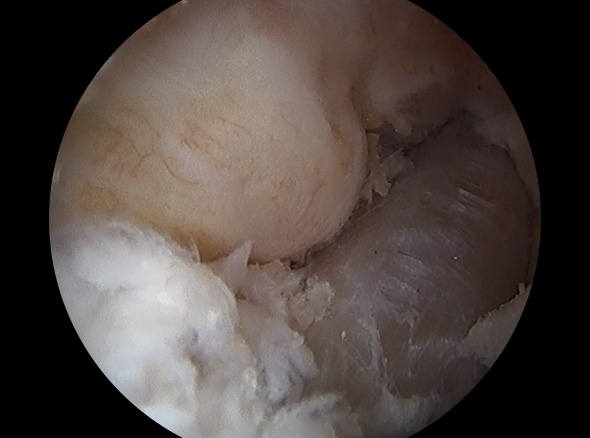

십자인대 재건술은 손상된 인대를 자가건이나 타가건을 활용해 원래의 인대의 위치에 재건하여 무릎의 기능을 회복시킵니다.

이식할 인대 삽입

이식한 인대 고정